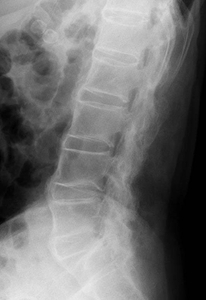

仙腸関節炎や脊椎炎による腰背部痛や臀部痛が初発症状となることが多いことが知られており、疼痛が運動により軽快し、安静や就寝により増悪する炎症性腰背部痛が特徴です。アキレス腱の付着部である踵部を始め、身体各所の靱帯付着部(関節周辺の骨性突出部など)の炎症徴候(疼痛、腫脹)がしばしば見られ、時に股、膝、肩など四肢の大関節の疼痛や運動制限も生じます。IL-17Aは、関節炎に特徴的な付着部炎において重要な役割を果たしていると考えられています(図2)。抗IL-17A抗体医薬品は、既存治療で効果不十分な尋常性乾癬、関節症性乾癬、膿疱性乾癬に対し治療効果が認められており、本邦でも強直性脊椎炎、X線所見を伴わない体軸性脊椎関節炎に対しても複数の製剤が承認されています。

希少難病である強直性脊椎炎は、病変部位では靭帯と骨との付着部位に炎症・骨化が起こり(図1)、疼痛、運動制限等がみられ、重症例では、体軸関節の強直をきたして日常生活能力の著しい低下をもたらします。FPP003は幅広い炎症性疾患に関与するタンパク質IL-17Aに対する抗体を誘導するペプチド治療ワクチンであり、強直性脊椎炎に代表される体軸性脊椎関節炎の新規治療選択肢となることが期待されます。

希少難病である強直性脊椎炎は、腰椎などの体軸関節で靭帯と骨との付着部位に炎症・骨化が起こり、疼痛、運動制限等がみられ、重症例では、体軸関節の強直をきたして日常生活能力の著しい低下をもたらします。FPP003は幅広い炎症性疾患に関与するタンパク質IL-17Aに対する抗体を誘導するペプチド治療ワクチンであり、強直性脊椎炎に代表される体軸性脊椎関節炎の新規治療選択肢となることが期待されます。